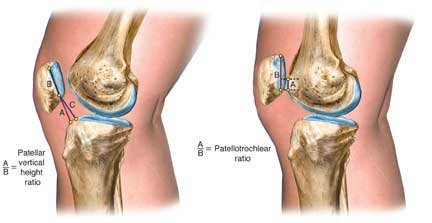

Serial lateral radiographs are taken to detect any decrease in patellar height for patients demonstrating limited patellar mobility or in whom an early arthrofibrotic response is detected. The height of the patella is measured as shown below.

On the left image, the numerator (line segment A) is the distance between the most ventral (anterosuperior) rim of the tibial plateau and the lowest end of the patellar articular surface. The denominator (line segment B) is the maximum length of the patellar articular surface. An alternative numerator (line segment C) locates the tibial reference point on the middle of the tibial plateau. The patellar vertical-height ratio equals A/B or C/B. Right, the numerator (A) is the superior most aspect of the trochlear cartilage that is in contact with line segment B. The denominator (line segment B) is the maximum length of the articular patellar surface. Using this method, the mean index is 32 + 12%, greater than 50% is a patellar infera, and less than 12% is a patella alta.